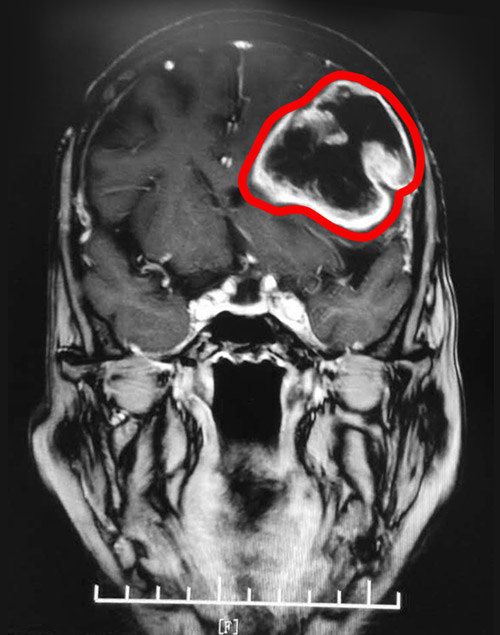

▲MRI影像顯示,患者左腦有一個(gè)大小約5.8*5.6cm的腫瘤

不查不知道,一查嚇一跳!MRI影像顯示,患者左側(cè)額顳頂葉存在大面積不規(guī)則形的低密度影,幾乎占據(jù)了左側(cè)大腦的一半位置。腦中線已發(fā)生偏移,病灶周圍明顯水腫。至此,一個(gè)大小約5.8*5.6cm的腦部腫瘤,終于現(xiàn)形了。